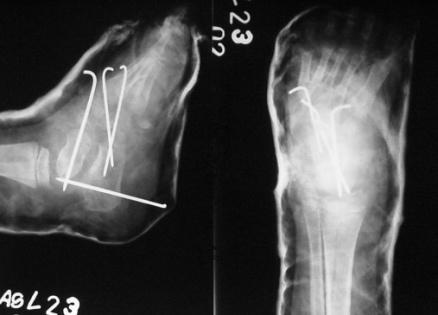

2. Older children with rigid clubfeet as well as the teratological vatiety require appropriate surgery.